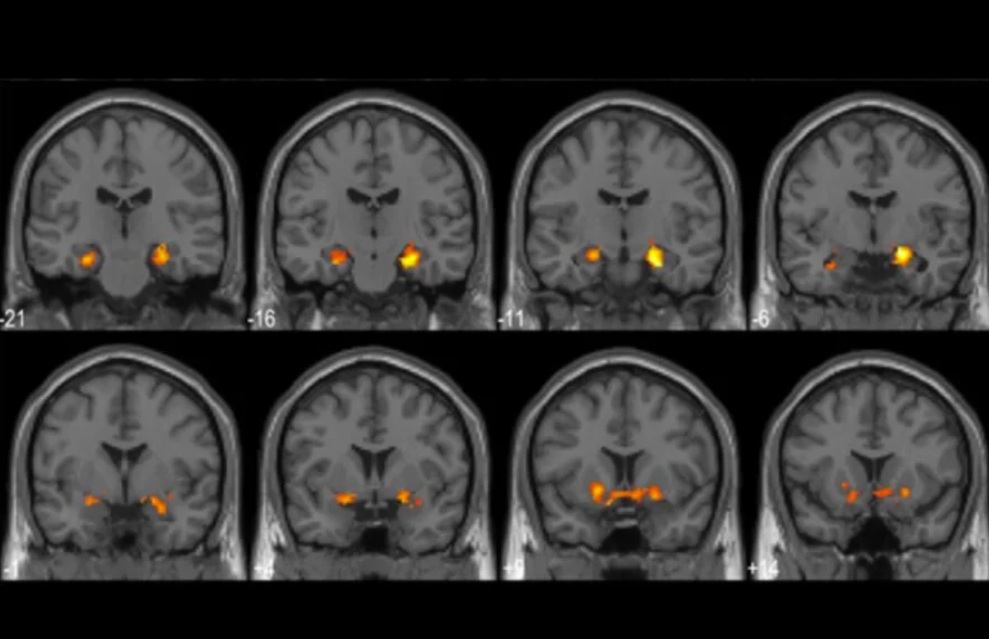

As study participants solved brain teasers, he [Cabeza] and his colleagues recorded their brain activity with functional magnetic resonance imaging, a technique that measures changes in blood flow associated with brain activity. The brain teasers were visual fill-in-the-blank puzzles that revealed a previously hidden picture once participants completed the image.

And the brain activity resulting from an a-ha moment was comparable to the brain characteristics of important insight events. This means that the solutions derived from a-ha moments were remembered more clearly and with greater detail than those derived from traditional solving or process of elimination-style solving. Some of the solvers still recalled their a-ha moment solution a full five days later!